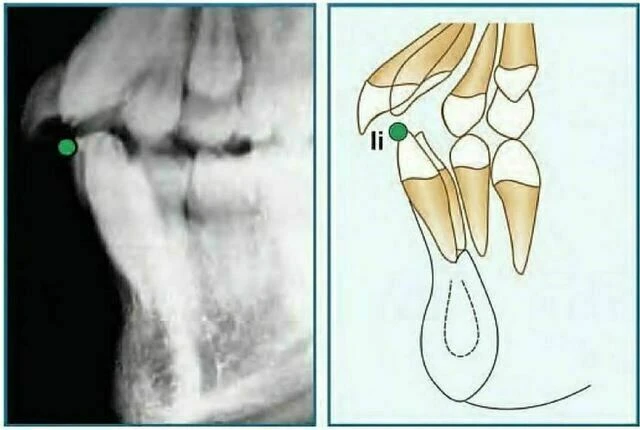

Insision Inferius (Ii): Đỉnh rìa cắn của răng cửa giữa hàm dưới nằm về phía ngoài nhất.